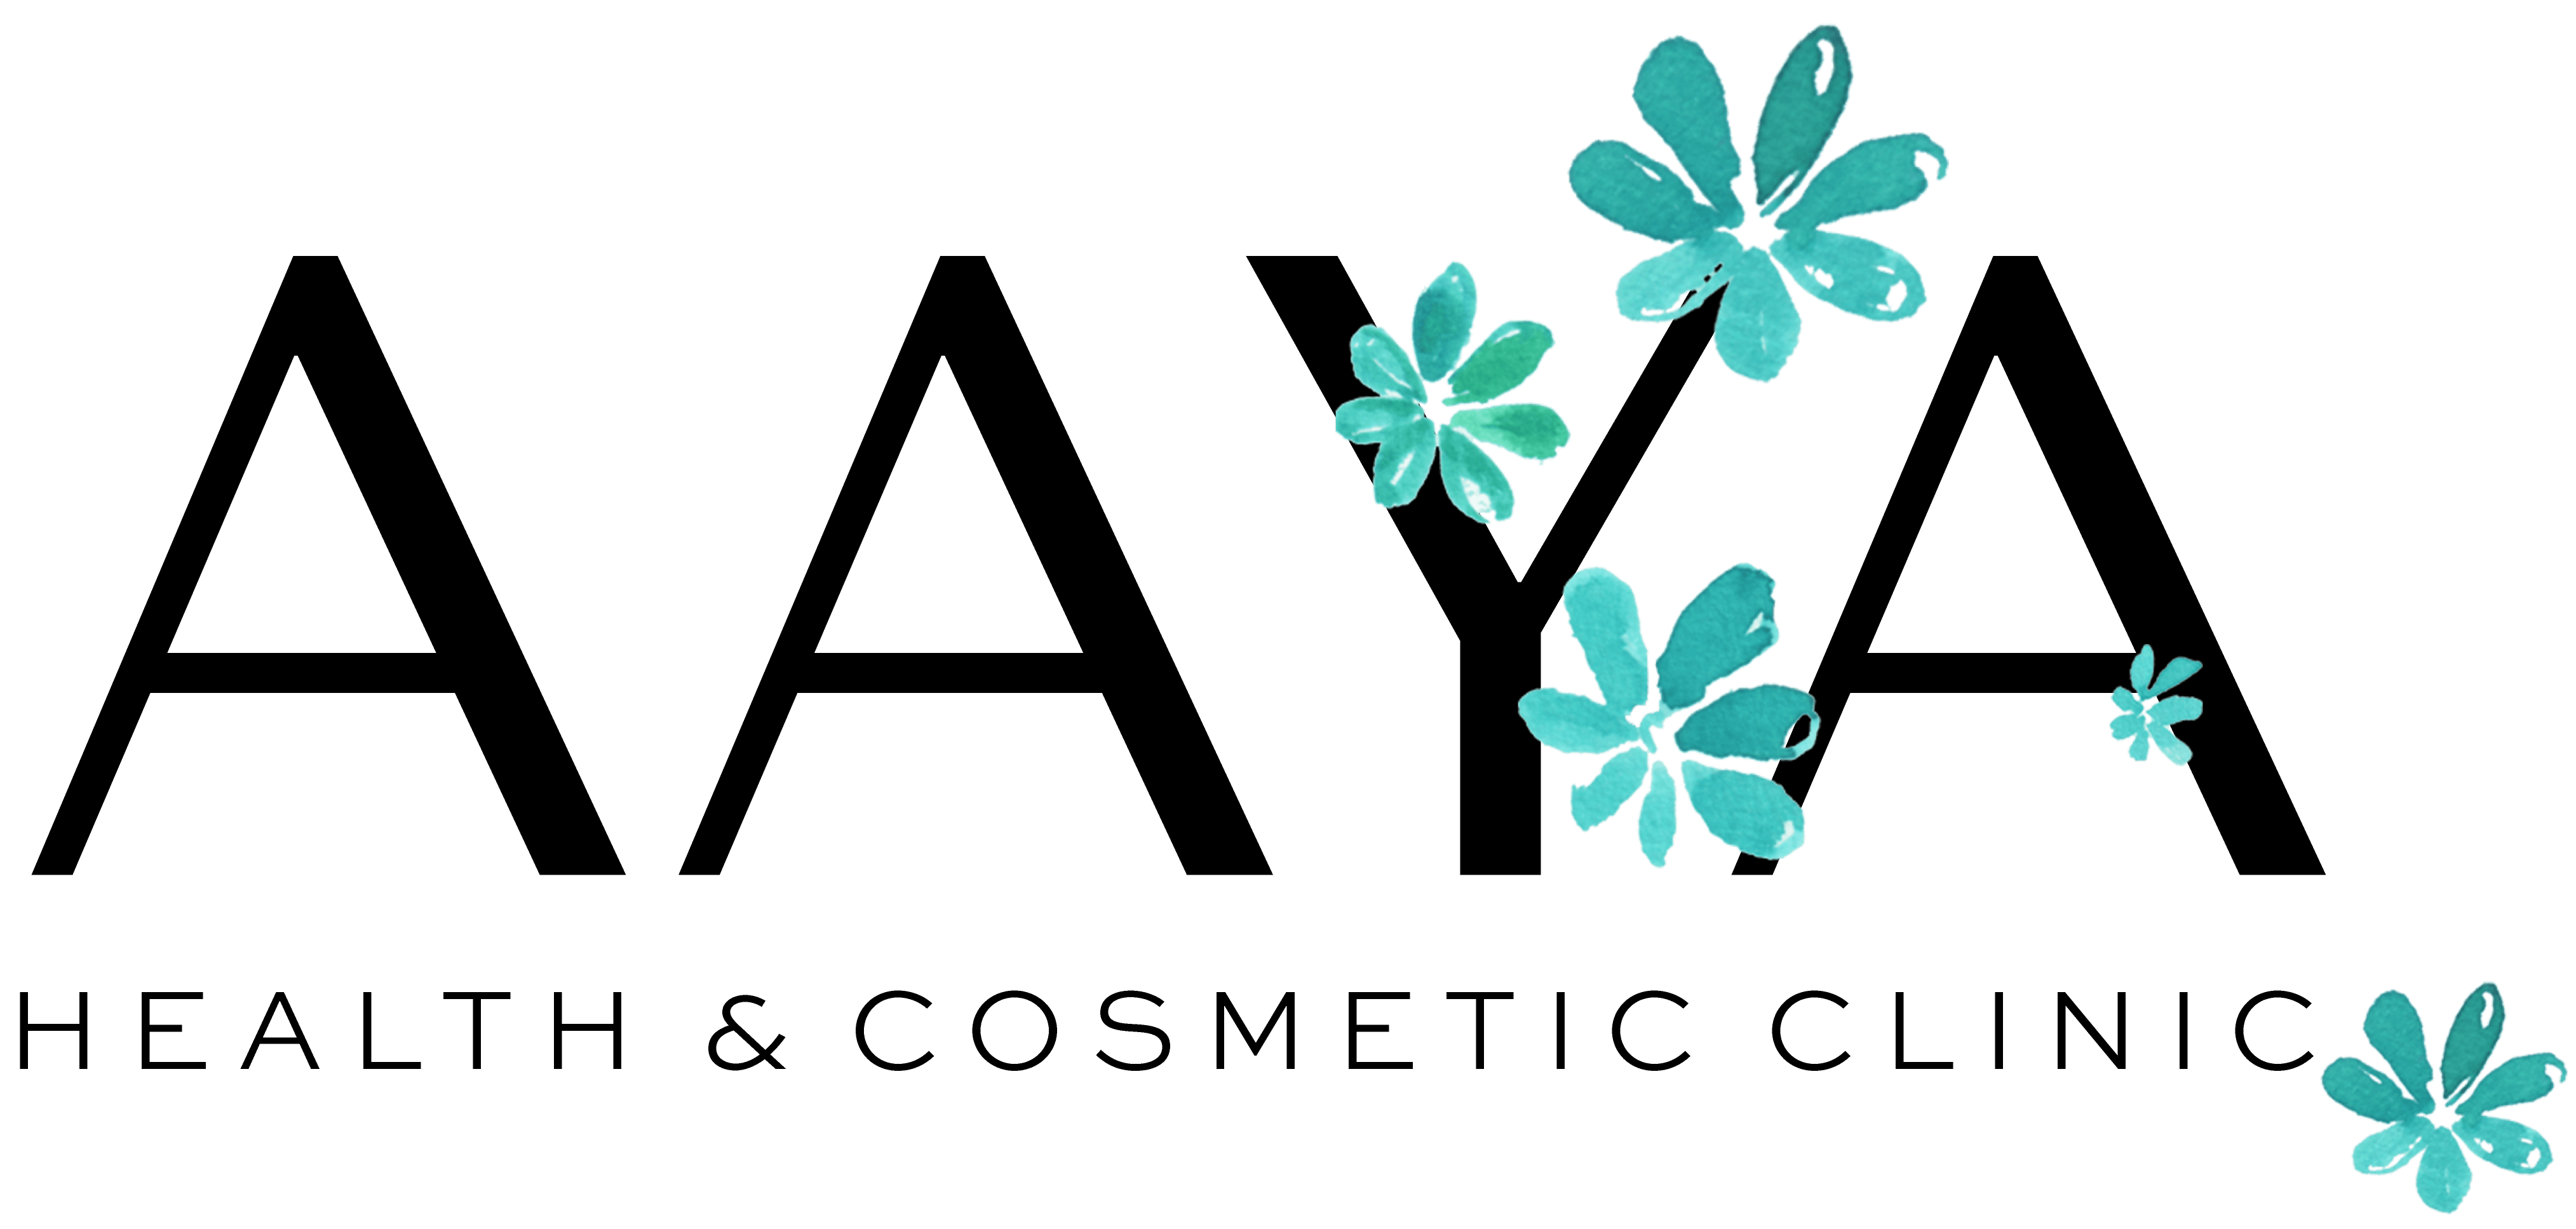

Omdat je met kennis, inzicht en aandacht grip op je gezondheid kan krijgen. En dat is in deze drukke maatschappij geen overbodige luxe. Omdat ook een veranderende levensfase zoals de overgang heel veel klachten kan geven. We luisteren, nemen de tijd en hebben de aandacht voor jou tijdens de checks. We brengen jouw ‘puzzelstukjes’ in kaart en analyseren jouw data. Bij AAYA doen we meer dan alleen bloedprikken, en dit is anders dan bij andere Health Checks. We beschikken over de juiste medische kennis en hebben een brede kijk (360 graden) op jouw gezondheid met behulp van onze 5 M’s (mind, motivation, motion, measurements, metabolics).

- Leefstijl vragenlijsten Motivation, Mind, Motion, Metabolics

- Uitgebreide AAYA vragenlijst om inzicht te krijgen in jouw leefstijl, slaap- en leefpatroon (Motivation, Mind, Motion, Metabolics)